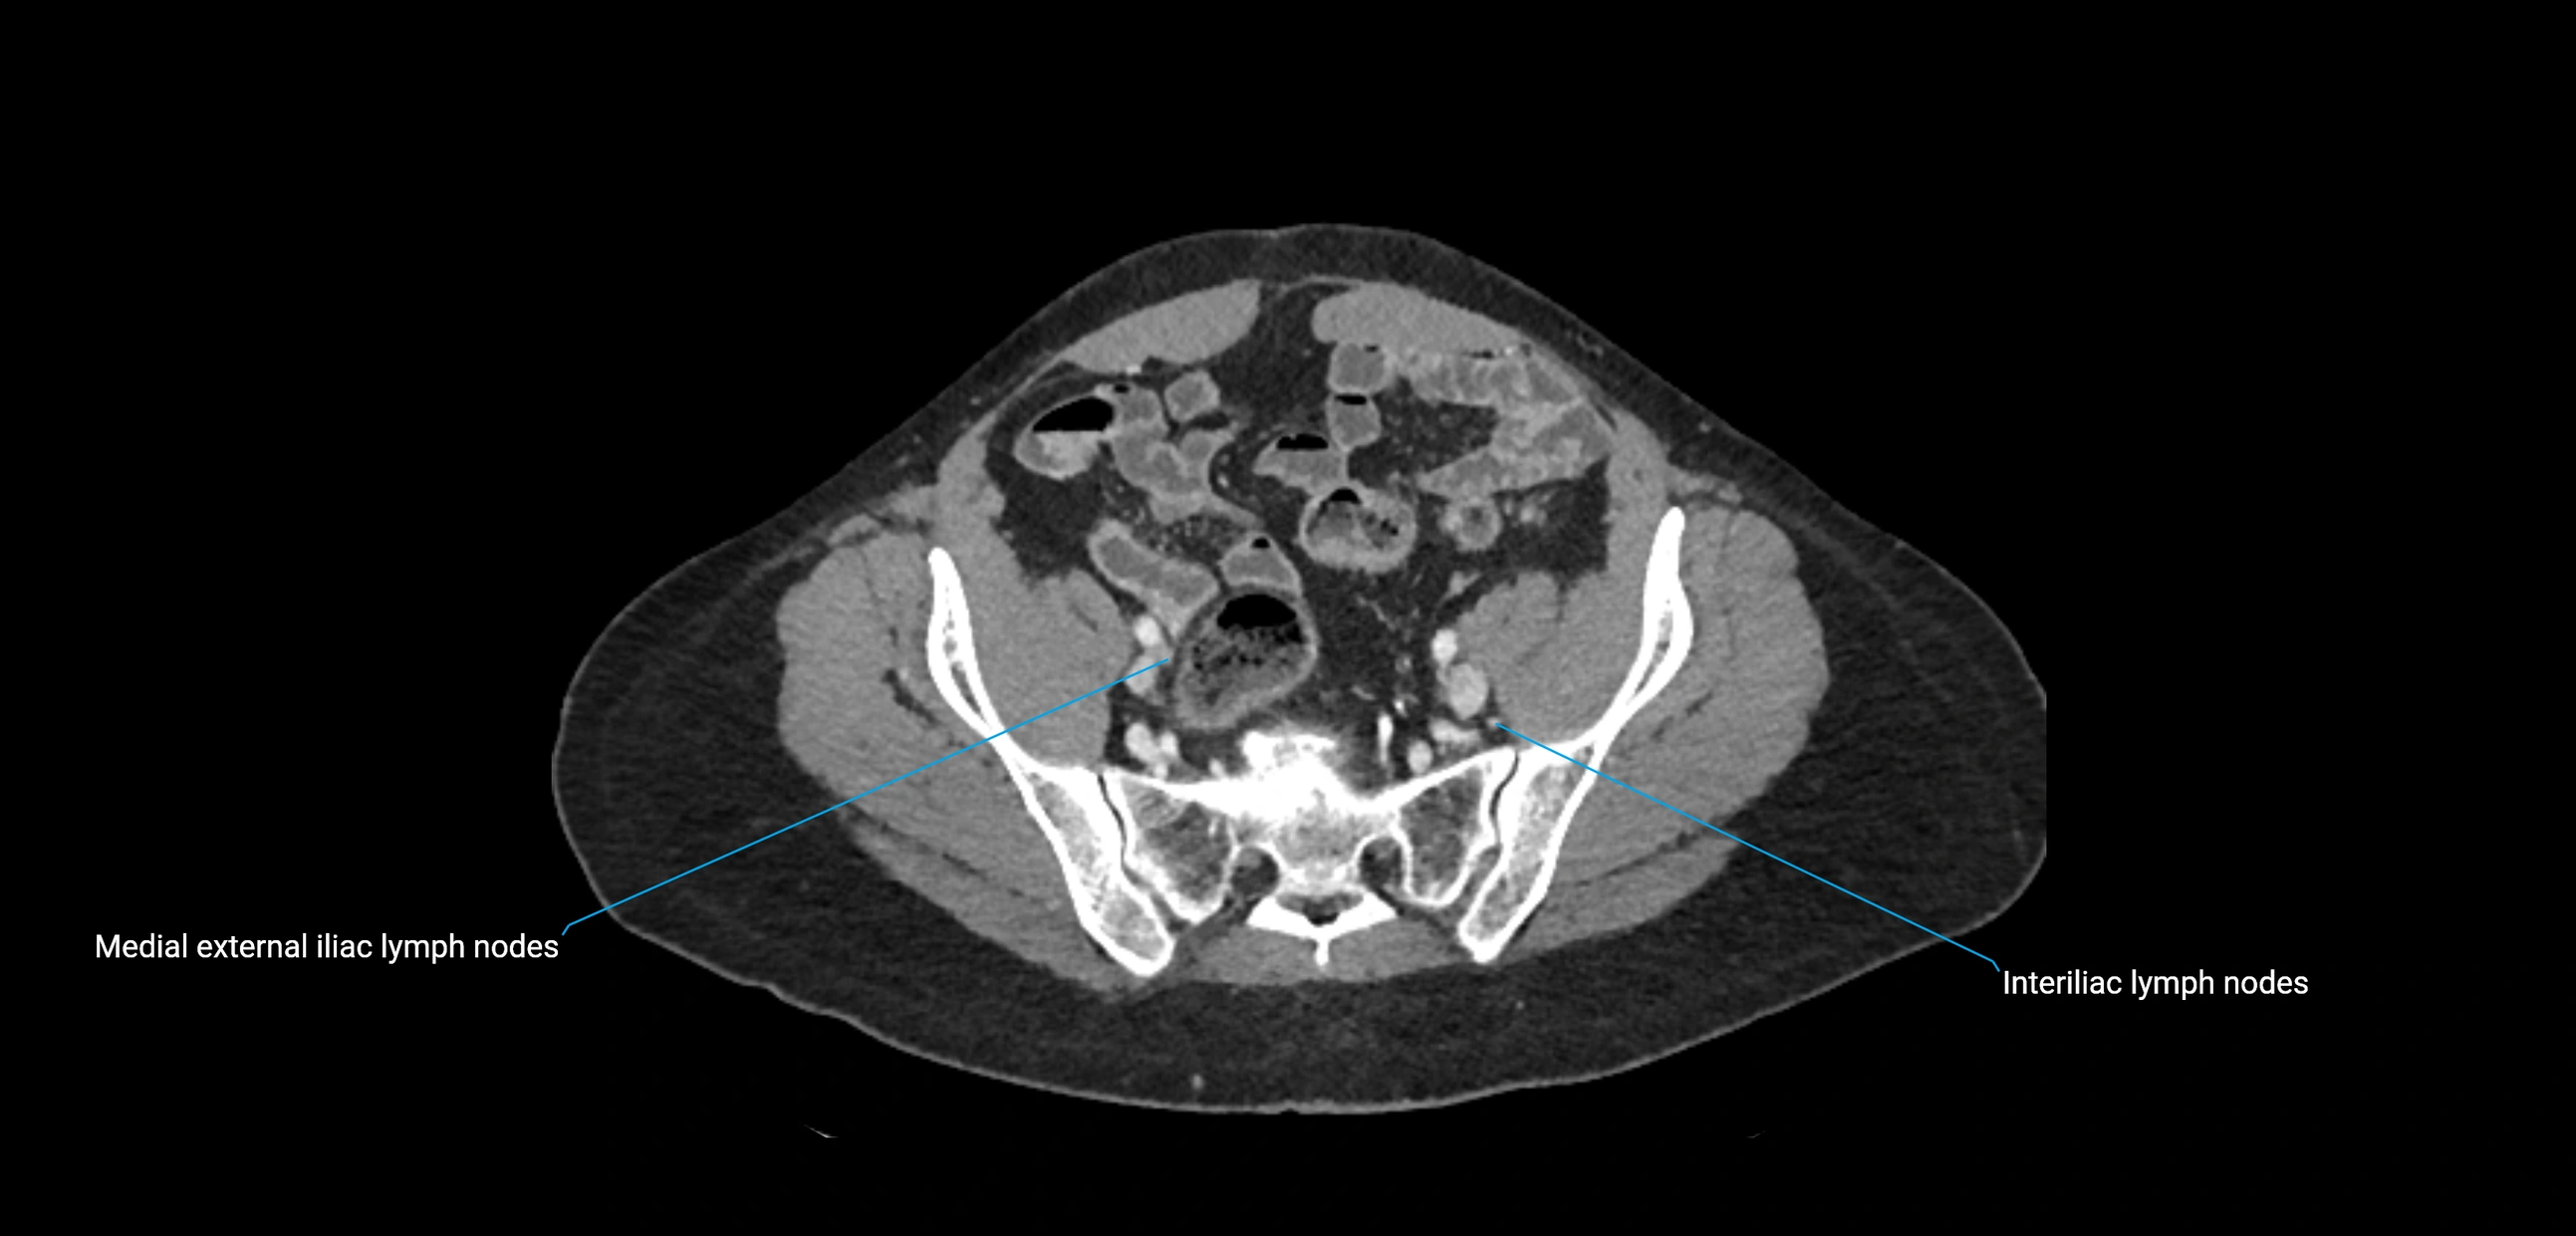

CT Venography (CTV):

• Demonstrates nodal encasement or compression of adjacent vessels (aorta, IVC, renal veins)

• Useful in staging testicular and ovarian malignancies

• Provides 3D reconstructions for retroperitoneal lymph node dissection planning